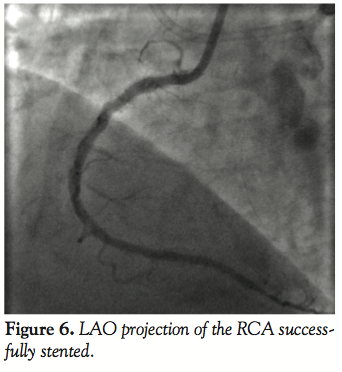

Case 2. A 50-year-old male with known occlusion of his RCA and inferior wall ischemia was referred for angiography. Bilateral femoral access with 8 Fr sheaths was obtained and simultaneous injections of the RCA and left coronary were performed (Figure 4) with a JR4 guiding catheter in the RCA. The CTO was successfully crossed using the antegrade approach and the GuideLiner catheter was then used to deliver long DES successfully (Figure 5). The final angiogram demonstrated the RCA successfully recanalized and a diffuse negatively modeled distal vessel (Figure 6).